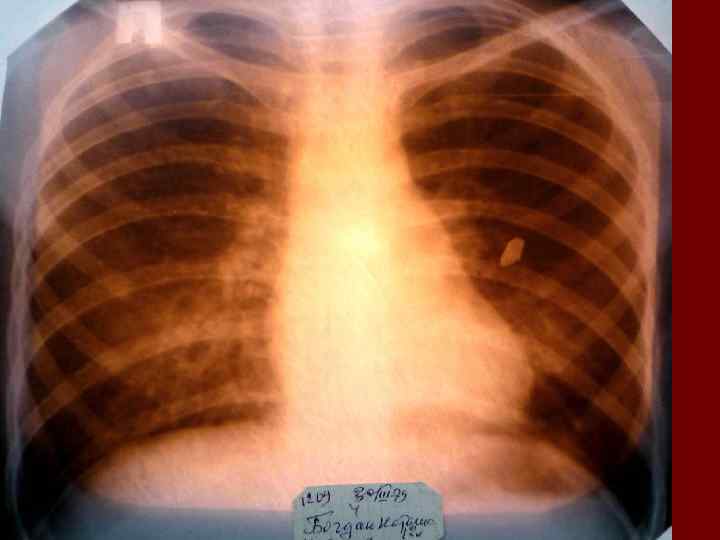

Долевая пневмония характеризуется лобарным пневмоническим инфильтратом. Крупозная ( пневмококковая) пневмония диагностируется прежде всего по клиническим данным. Крупозная пневмония сохраняет свою типичную картину пневмококковой пневмонии: острое начало с характерными клиническими данными, циклическое течение, несклонность к деструкции, гомогенной и лобарной инфильтративной тенью при рентгенологическом исследовании. Вместе с тем, широкое использование антибиотиков способствовало значительному снижению числа крупозных пневмоний у детей. Интерстициальная – редкая форма пневмоний, при которой оказывается поражен прежде всего интерстиций. Как правило, интерстициальная пневмония обусловлена вирусами, пневмоцистами, внутриклеточными микроорганизмами и грибами.

Морфологическую форму пневмонии определяют по клинико – рентгенологическим данным: выделяют очаговую, очагово – сливную, долевую ( крупозную), сегментарную и интерстициальную пневмонии. Очаговая – наиболее распространенная форма. Пневмонические очаги чаще бывают размером 1 см и более. Очагово – сливная – инфильтративные изменения в нескольких сегментах или во всей доле легкого, на фоне которых могут быть видны более плотные участки инфильтрации и/или полости деструкции. Сегментарная – в процесс вовлекается весь сегмент, который, как правило, находится в состоянии гиповентиляции, ателектаза. Морфологическая картина воспаления при очаговых и сегментарных пневмониях связана с первичным инфекционным воспалением в бронхах, что дает основание отнести эти варианты поражения легочной ткани к бронхопневмониям, нередко сопровождающихся бронхообструктивным или бронхообтурационным синдромами. В настоящее время данный тип пневмоний у детей встречается наиболее часто.